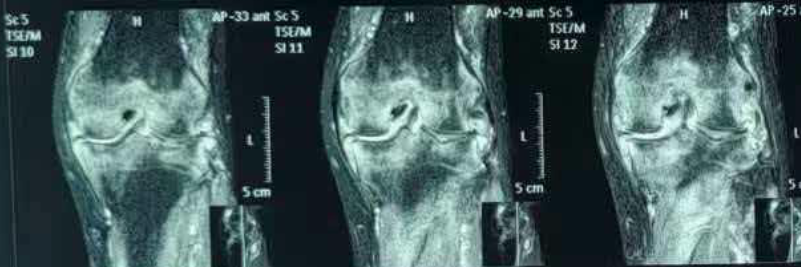

2月前,患者就诊于当地医院骨科,化验虎红平板凝集试验阳性,试管凝集试验:滴度≥1:160,PCR检测阳性。完善膝关节磁共振,在失状位可见:股骨、胫骨下斑片状、弥漫样高信号,提示骨髓水肿/炎性浸润(图1),股骨前方、股四头肌腱下方高信号,提示髌上囊积液(图2)。

图1. 股骨、胫骨下斑片状、弥漫样高信号,提示骨髓水肿/炎性浸润